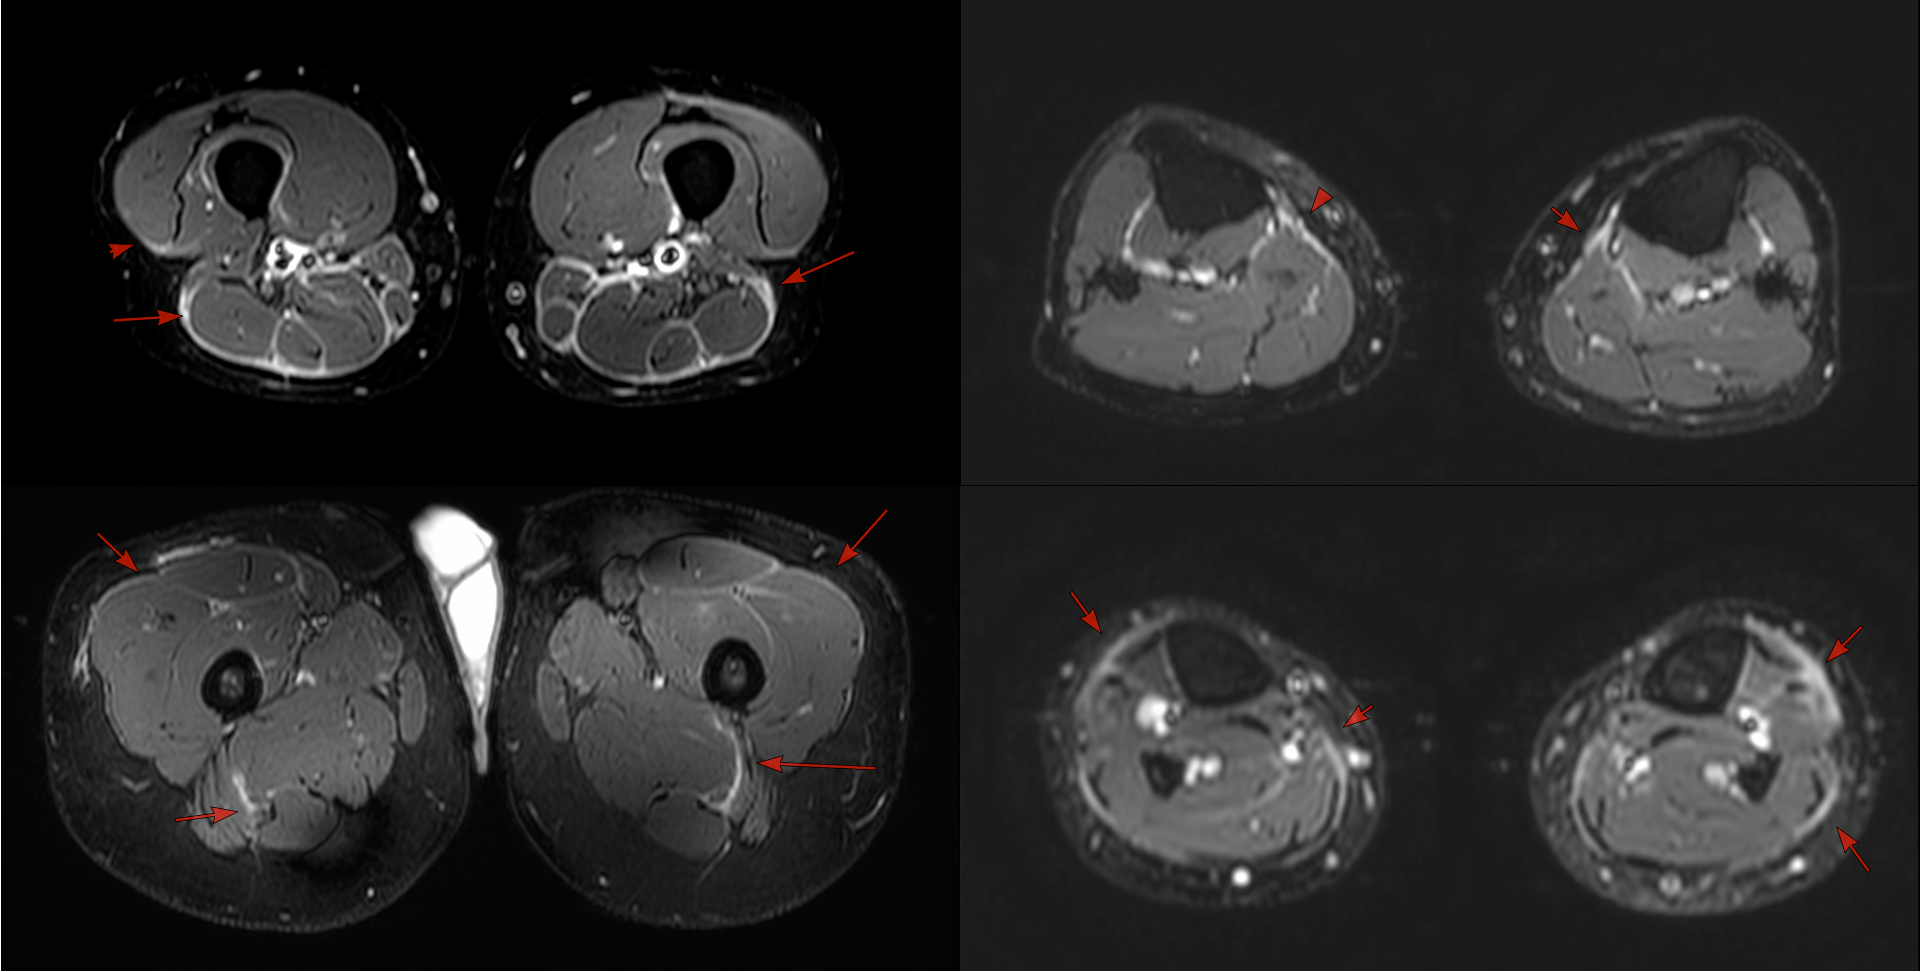

Case 62: The Symmetric Fascial Edema Pattern of Dermatomyositis

35-years old with dermatomyositis

35-years old man with dermatomyositis and limb pain on treatment came for a baseline myositis protocol MRI, which showed symmetric fascial edema as depicted in the images below.